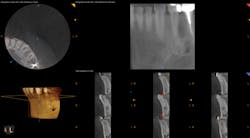

To determine whether tooth No. 21 or No. 22 was the issue, two periapical radiographs were taken. However, the results were inconclusive (figures 2–4). With clinical testing and 2-D radiographs providing no smoking gun, it was decided to use limited field-of-view CBCT (Carestream Dental CS 9000C 3D) on the region. CBCT revealed that tooth No. 22 was abscessed and a fair amount of the apical bone was completely gone (figures 5 and 6). In fact, since the time the pain began and when the patient presented at the practice, the tooth had abscessed at an alarming rate and was now considered an emergency situation.

Figure 5: CBCT showing the periapical lesion on No. 22 in multiple slices on the lower right-hand side of the image